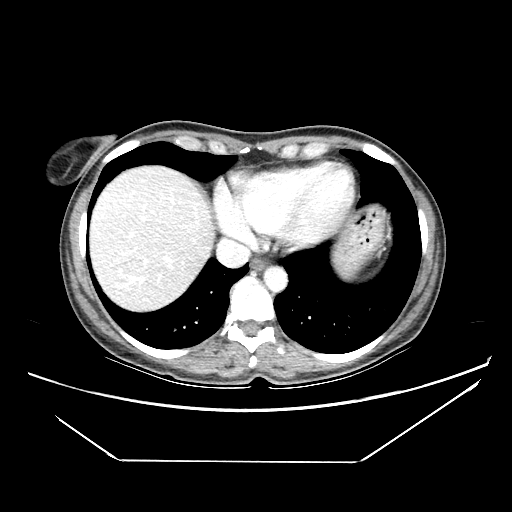

Generated VENOUS CT scan (A→B translation)

Full window (WL 1023.5, WW 4095 β†’ Low βˆ’1024, High +3071)

Actual HU range: [-811.5, 753.5]